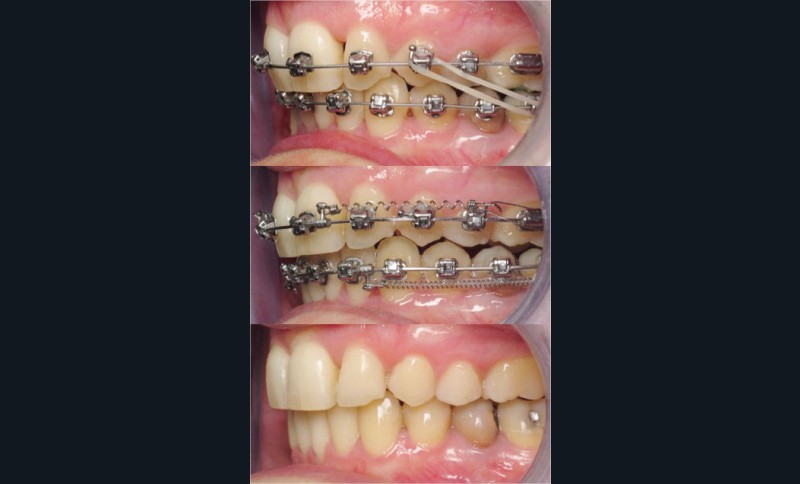

Un appareillage Damon métal a été mis en place, réalisé à partir d’un set up numérique Insignia pour obtenir un contrôle précis des torques et de la forme d’arcade et réduire le temps de finition grâce à un collage indirect très précis.

De larges surélévations postérieures étalées ont été mises en place et la patiente a porté des élastiques précoces suivant les principes de la technique Damon. Les 14 et 24 rempliront le rôle des 13 et 23.

L’objectif, en utilisant la technique Insignia est de réduire le temps de traitement de 28 à 18 mois avec 12 rendez-vous (fig. 5 à 14).

Les objectifs de traitement ont été remplis. Nous avons observé un excellent contrôle du torque et une absence de perte de l’occlusion postérieure grâce à la technique Insignia.